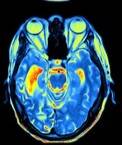

Een doorbloedingsscan, Pet-scan (Positron Emission Tomography)

of SPECT scan (Single Photon Emission Computed Tomography) toont het functioneren aan, of er bijvoorbeeld een doorbloedingsstoornis of verhoogde activiteit is. Het spoort dus veranderingen in bloedstroom en metabolisme in hersenen. Hiermee is diffuus letsel vaker wel zichtbaar te maken maar ook niet altijd.

• de SPECT scan, maakt ook gebruik van kleine hoeveelheden radioactieve materialen die in bepaalde weefsels of organen ophoopt zodat er een afbeelding van kan worden gemaakt.  De radioactieve stoffen verdwijnen snel uit het lichaam en zijn niet schadelijk.